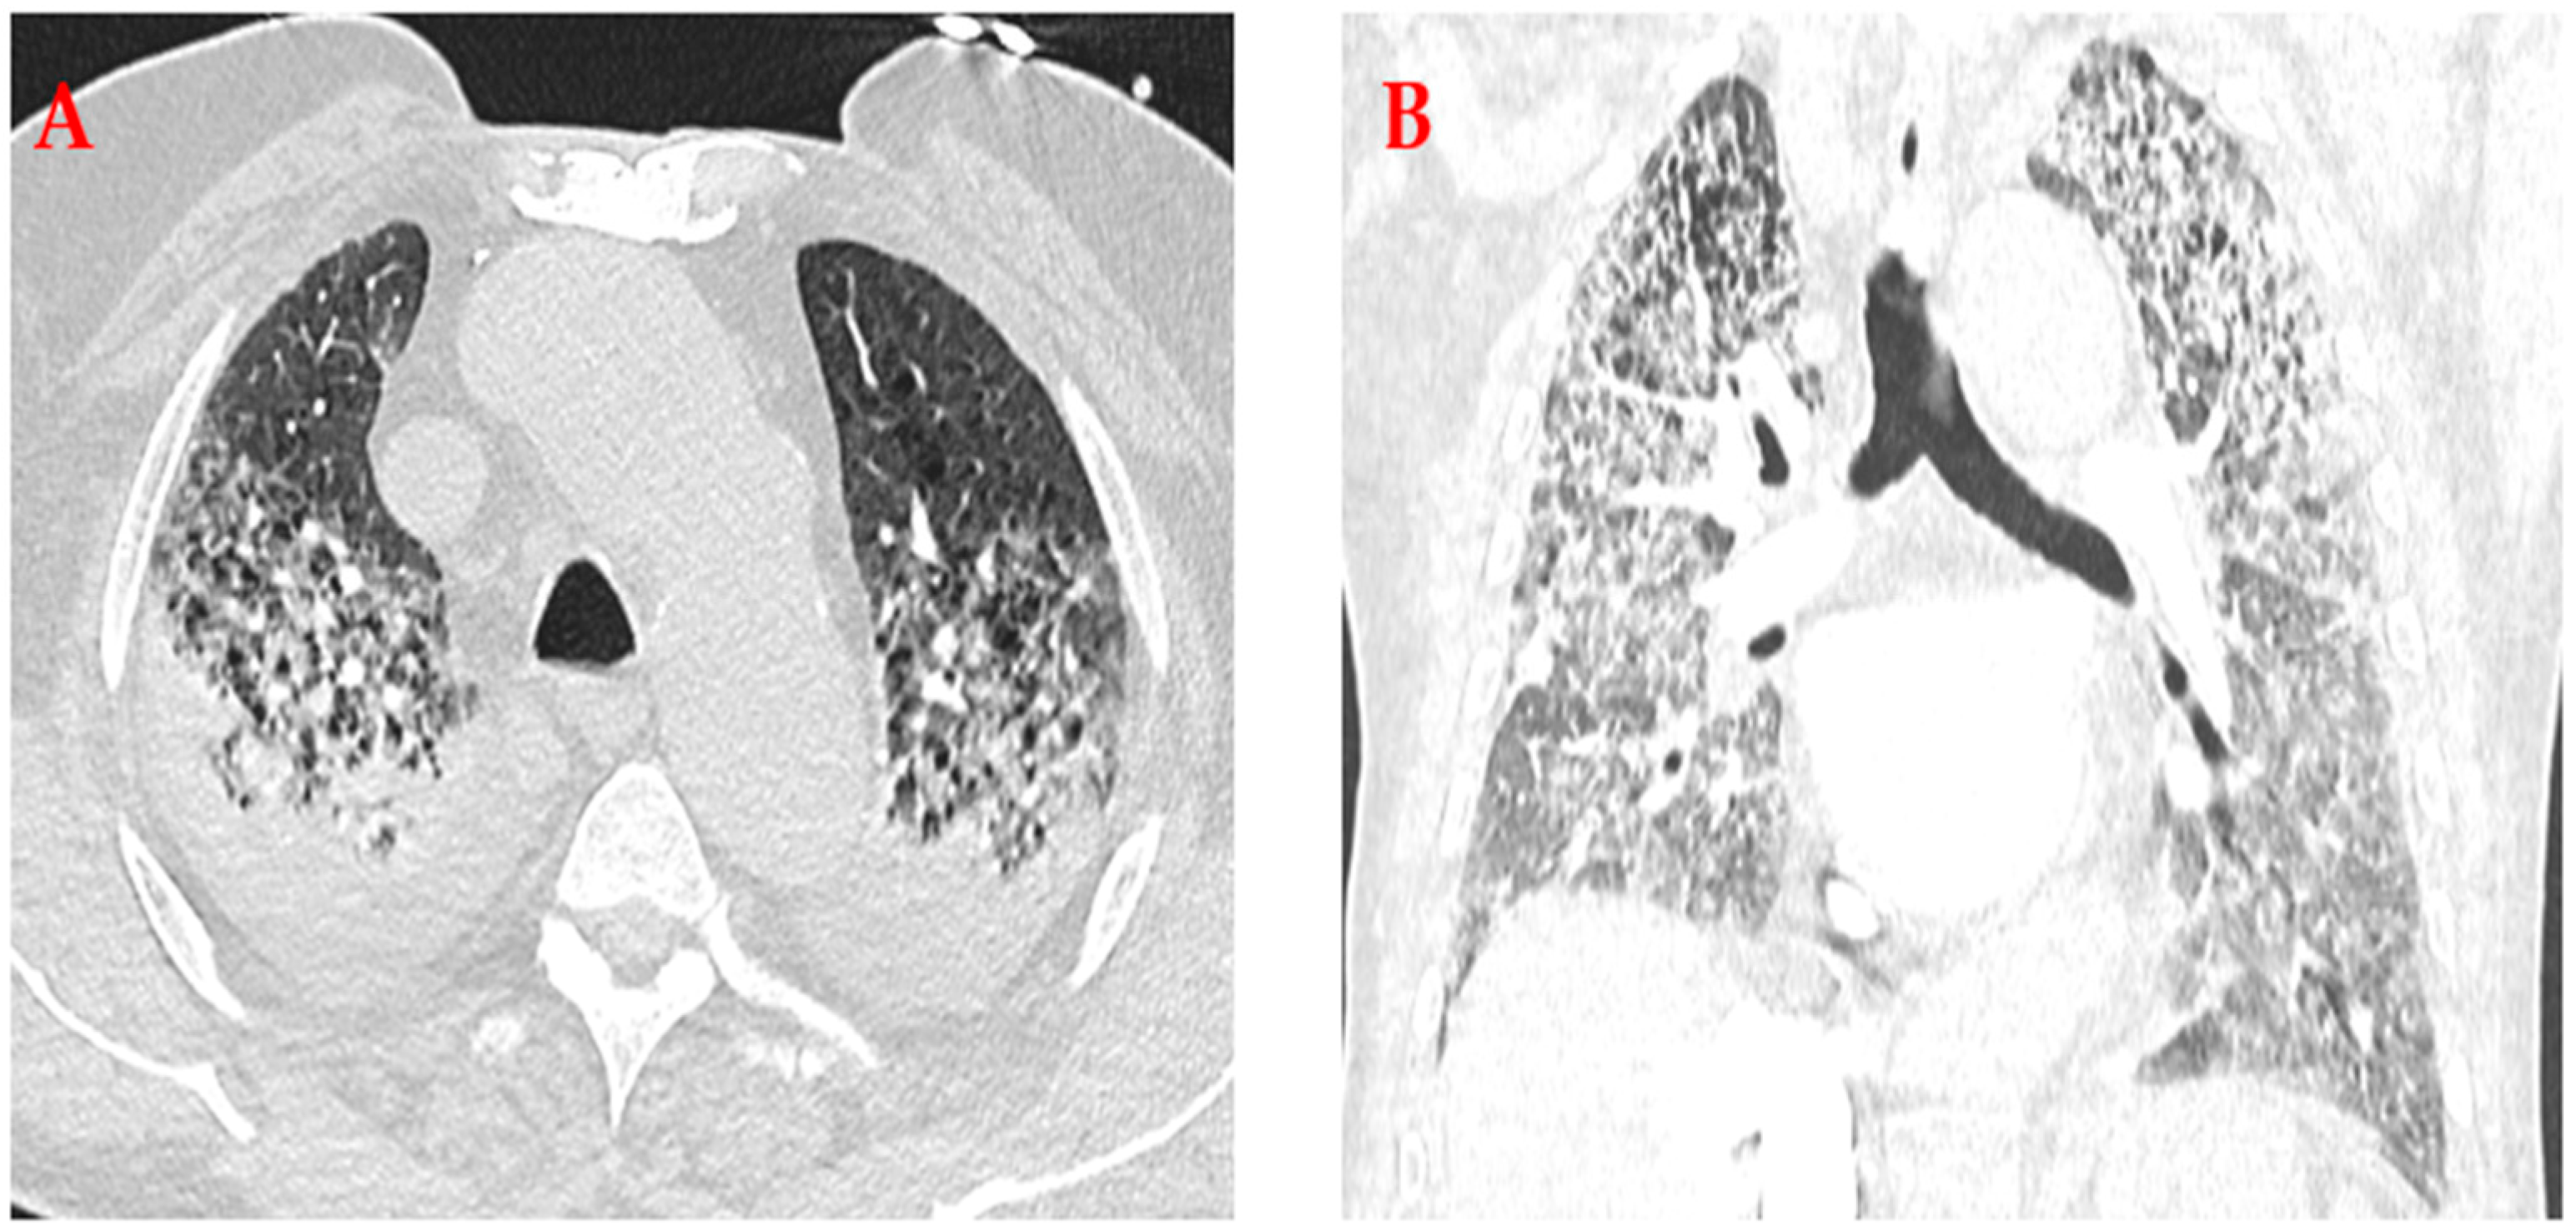

2. Case Presentation